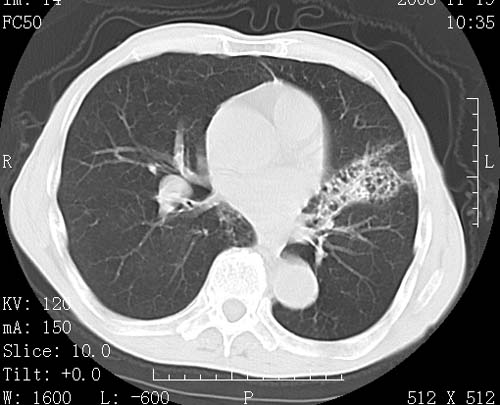

标题: CT16691:m 67 胃镜确诊食管下段及贲门癌 [打印本页]

标题: CT16691:m 67 胃镜确诊食管下段及贲门癌

术前查体,双肺部结节是转移?结核?请点评

1)符合食管癌表现。2)两肺及纵隔淋巴结多发性转移瘤。3)左肺上叶舌段及两肺下叶炎症感染。

食管癌伴双肺转移,评述:肺部毛细血管网丰富,全身血液均快速流经肺部,癌细胞容易过滤定植,形成转移瘤,影象特点为以毛细血管末梢为中心的结节灶,边缘光滑锐利,少见有中心空洞着,不同来源的转移瘤可有各自特点,如甲状腺癌为双肺弥漫性微结节,本例有原发灶,双肺影象灶典型,左肺舌段条带状网格样伴胸膜天幕征,可视为癌性淋巴管炎。

符合食管癌表现。两肺及纵隔淋巴结多发性转移瘤。双肺还有支扩表现.

左肺舌段有斑点钙化灶,能否说明是结核而不是转移?如果是转移将放弃手术改成化疗,如果是结核将考虑择期手术